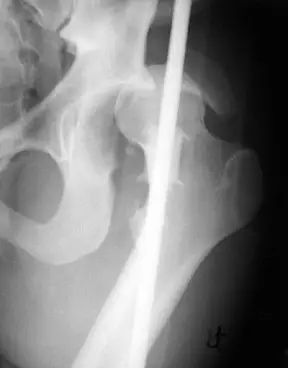

20歲男性病人因車禍左髖關節腫痛。圖為本次就診之左髖關節 X 光攝影及電腦斷層影像。最可能的診斷為何?

從骨盆正位X光片可見左側股骨頭與 acetabulum 失去正常對位關係,股骨頭相對於右側明顯向上、向後且輕微外隱,股骨小轉子在AP投影中不明顯,暗示內旋位置。左側股骨頭尺吋於幾何放大下比右側小,符合股骨頭後方移位的特徵(radiopaedia.org)。

進一步於 axial CT 平掃中,可見左股骨頭完全移出髖臼,位於 posterior acetabular rim 之外,且緊鄰一塊骨片,代表 posterior rim fracture。周邊尚見關節腔內軟組織密度,符合急性髖關節骨折脫位的表現(radiopaedia.org)。